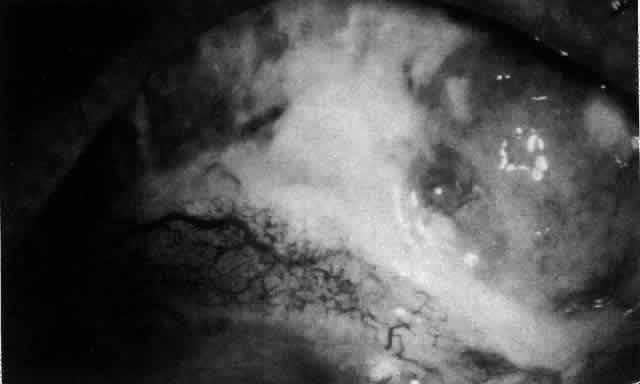

The redness of simple episcleritis may be intense, varying from a fiery-red or a brick-red discoloration to a mild red flush, but it does not have the bluish tinge that is seen in scleritis. The distribution is usually sectorial but can involve the whole anterior segment of the globe. The episcleral vessels are engorged but retain their normal radial position and architecture (Figs. 13 and 14; Color Plate 1A). In simple episcleritis, there is a diffuse edema of the episcleral tissues. These tissues are sometimes infiltrated with gray deposits that appear yellow in red-free light. Surprisingly, the eye is rarely tender to the touch.

Fig. 13. Infiltration of the episclera in which the superficial episcleral vessels show maximal congestion. Conjunctival vessels are slightly congested, as is the deep episcleral plexus, whose irregular criss-cross pattern can be seen deep to the radially arranged superficial episcleral plexus.

Fig. 14. Diffuse inflammation. Superficial vessels are maximally engorged and retain their radial pattern and architecture. (See Figures 27 and 34.) (Watson PG: Connective tissue disorders and the eye. In: Recent Advances in Ophthalmology, Vol 5, pp 214–277. London, Churchill-Livingstone, 1975)